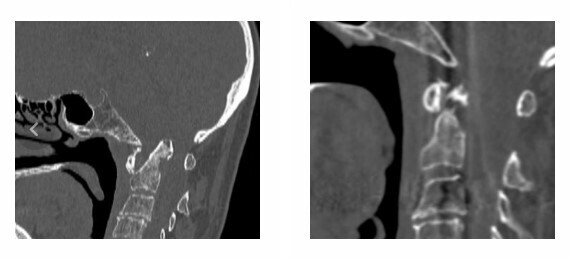

Спасать пациентку пришлось нейрохирургам из Херсонской областной клинической больницы. МРТ подтвердило, что у женщины были сломаны первый и второй шейные позвонки и разорваны связки, которыми голова крепится к верхнешейному отделу позвоночника.

"Жизнь пациентки буквально висела на волоске. В любую минуту могло произойти смещение зубовидного отростка второго шейного позвонка с повреждением жизненно-важных центров ствола головного мозга", – рассказывают врачи.

По их словам, остеопороз у пациентки не позволял надеяться на удачное сживление позвоночника с минимальным вмешательством. Поэтому женщине была проведена двухэтапная операция. На первом этапе были вправлены вывихнутые позвонки, ствол головного мозга и спинной мозг освободили от компрессии. На втором этапе были вживлены титановые конструкции. В ходе операции титановыми системами было зафиксировано правильное положение головы по отношению к позвоночнику и предотвращено повреждение спинного и головного мозга.